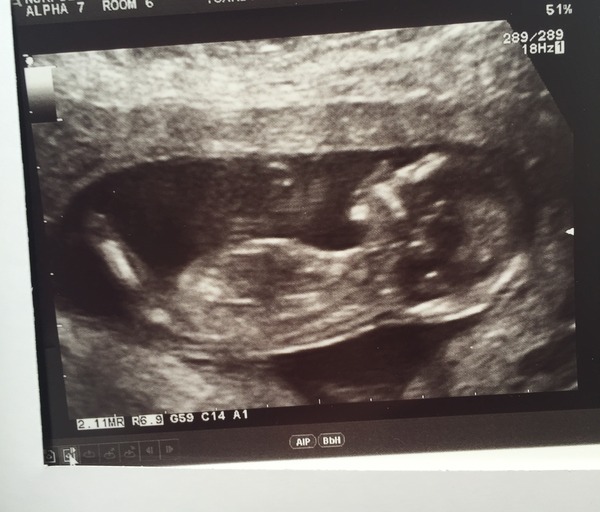

Beth2511 · 07/04/2016 19:16

Hi all, would also like to join in.

Good scan today with a edd of 13th october.

Any guesses on the nub??

Beth that looks like a blue nub to me!